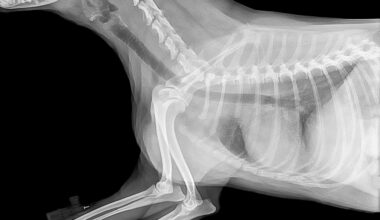

Images or infographicsresources from reputable organizations for accurate visuals that align with your article.